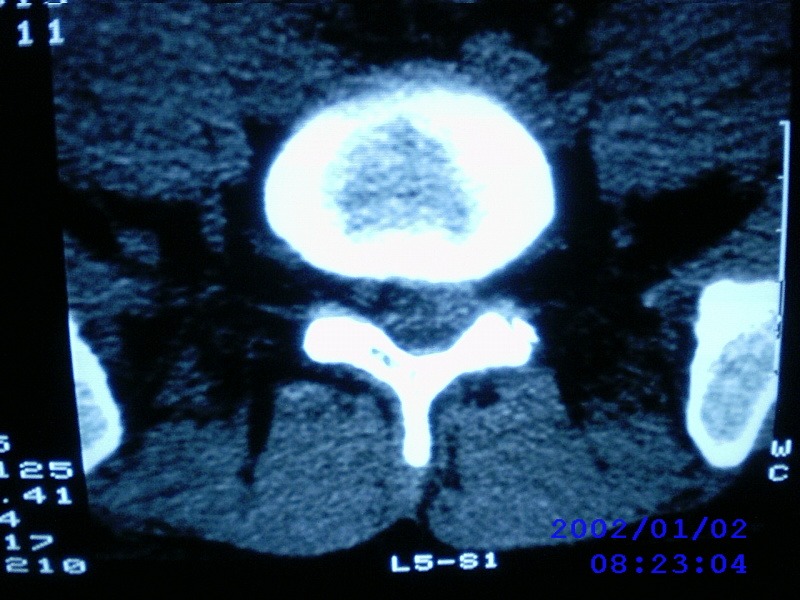

患者,男性,40岁,腰痛伴左下肢疼痛、麻木6年。5年前做过腰椎间盘手术,具体是哪个位置病人记不清了。

我拍的是l4-5、l5-s1

l4-5/l5-s1都做过。又有突出了

1)l4/5及l5/s1左侧椎板术后改变。2)l5/s1椎间盘突出,l5椎体下缘许莫氏结节。3)l4/5椎间盘膨出并突出。4)l3/4椎间盘膨出。

1)l4/5及l5/s1左侧椎板术后改变。2)l5/s1椎间盘突出,l5椎体下缘许莫氏结节。3)l4/5椎间盘膨出并突出。

1)l4/5及l5/s1左侧椎板术后改变。2)l5/s1椎间盘突出,l5椎体下缘许莫氏结节。3)l4/5椎间盘膨出并突出。4)l3/4椎间盘膨出。支持!